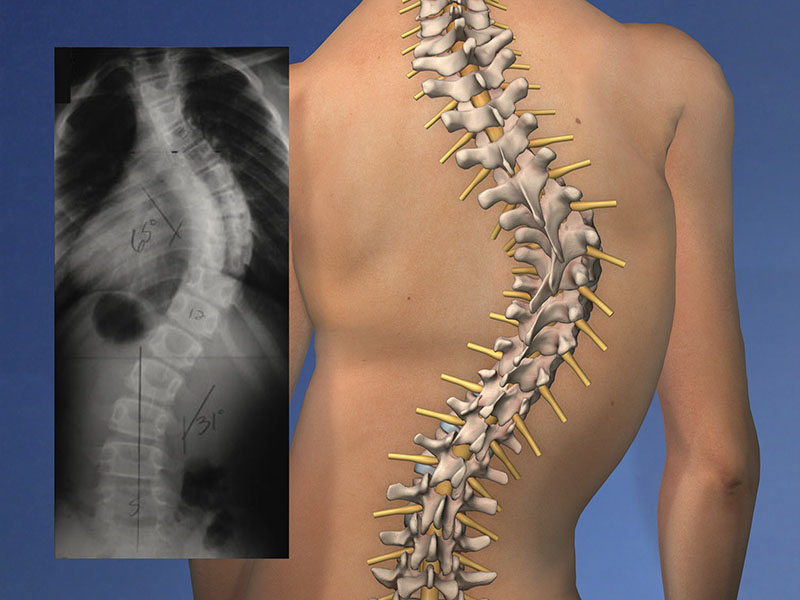

Scoliosis is abnormal side-to-side curvature of the spine. The spinal curve may develop as a single curve (shaped like the letter C) or as two curves (shaped like the letter S). In children and teens, scoliosis often does not have any noticeable symptoms and may not be noticeable until it has progressed significantly. The two most common forms are degenerative scoliosis and idiopathic scoliosis (adolescent). Three orthopedically approved options exist for combating scoliosis: observation, bracing, or surgery.

Measuring and Tracking Scoliosis Curves

The orthopedic surgeon may order an X-ray of the spine and use the "Cobb method" - an extremely accurate measuring technique - to calculate the curvature of the spine and its progression. Curves that are less than 10 degrees are not considered to represent scoliosis but are considered to be spinal asymmetry. These types of curves are extremely unlikely to progress and generally do not need any treatment, but the child's physician should continue to monitor the curve during regular checkups. Curves beyond 20 to 30 degrees in a growing child should be observed at 4 to 6 month intervals by an orthopedic surgeon with expertise in scoliosis. In a patient that is still growing, treatment will be needed if the following factors are present: The spinal curve progresses more than 5 degrees during a typical period of observation, or; the spinal curve has already reached 30 degrees or more. If the curve progresses less than 5 degrees during a specified period of observation, the physician may determine that the curve is not worsening rapidly enough to cause deformity, and treatment may not be necessary.